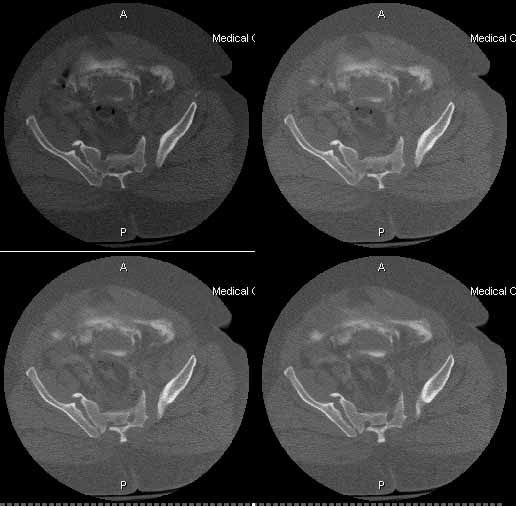

The patient is a 63 yo man who was crushed at work 5 days ago and sustained an unstable pelvic fracture with a GU disruption. I have assumed his care today. I am told he has an extraperitoneal bladder rupture but based on the cysto I am concerned about a urethral disruption. He does not otherwise have any significant injuries or medical problems, but he is severely obese (350 lbs+). Xrays and CT cuts are enclosed.

Five dayslater we was doing much better and was deemed fit for surgery. The site of his SP tube had completely healed up without evidence of infection. We took him to the OR to plate his symphysis, making our Pfannenstiel incision low to avoid the SP site. During plating we notice at one point some murky fluid in a little pocket deep inside his pelvis. The was sent for gram stain and culture and came back GPC and ultimately grew out enterococcus. We completed the symphseal plating & packed the wound with antibiotic beads. We brought him back at 48 hours for repeat I&D and removal of the beads and closure. He tolerated both of these surgeries well. About 5 days later(roughly 2 1/2weeks afterhis injury)his wound in the front was looking good and there was no evidence for infection. So he was brought back to the OR for posterior pelvic fixation. My plan had been to do an ORIF and place SI screws, but I couldn't get adequate inlet or lateral views. So we did an open reduction and posterior transiliac plating. The reductions in the front and the backwere difficult due to both his size and due to the time that had elapsed since his injury.I've enclosed pre and post xrays.